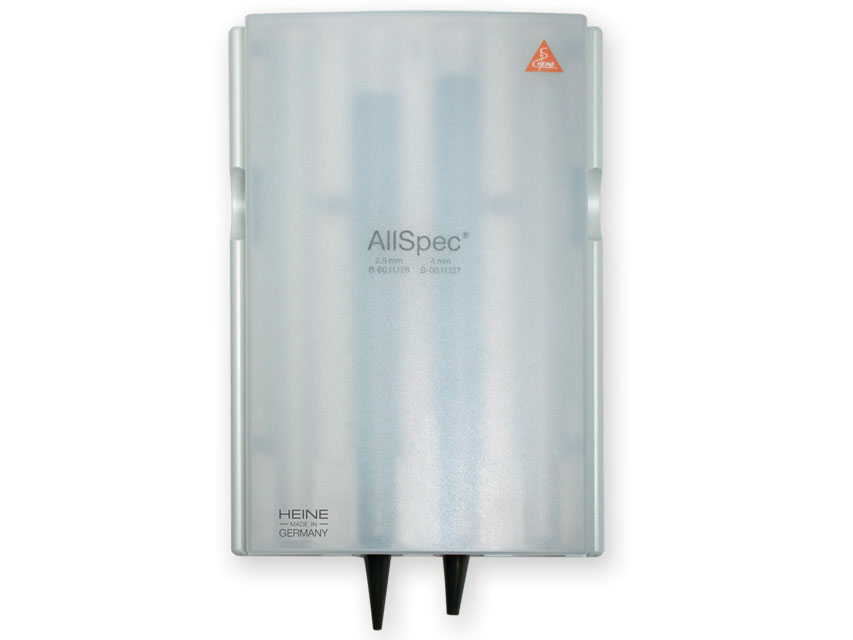

All’interno sono disponibili curettes auricolari, speculum auricolari e speculum nasali, strumenti essenziali utilizzati per l’esame e il trattamento delle vie uditive e nasali in contesti sanitari e professionali.

All’interno sono disponibili curettes auricolari, speculum auricolari e speculum nasali, strumenti essenziali utilizzati per l’esame e il trattamento delle vie uditive e nasali in contesti sanitari e professionali.